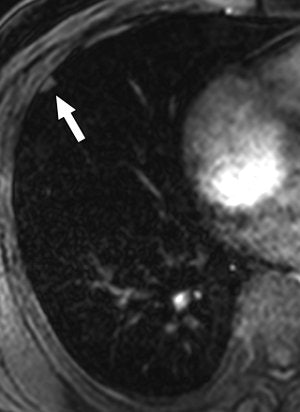

| Same patient as above. T1-weighted 3D turbo field-echo (B) and T2-weighted triple inversion black blood turbo spin-echo (C) images show 9-mm nodule (arrow) in right middle lobe. Nodule is subtle in C and not easily visualized. |